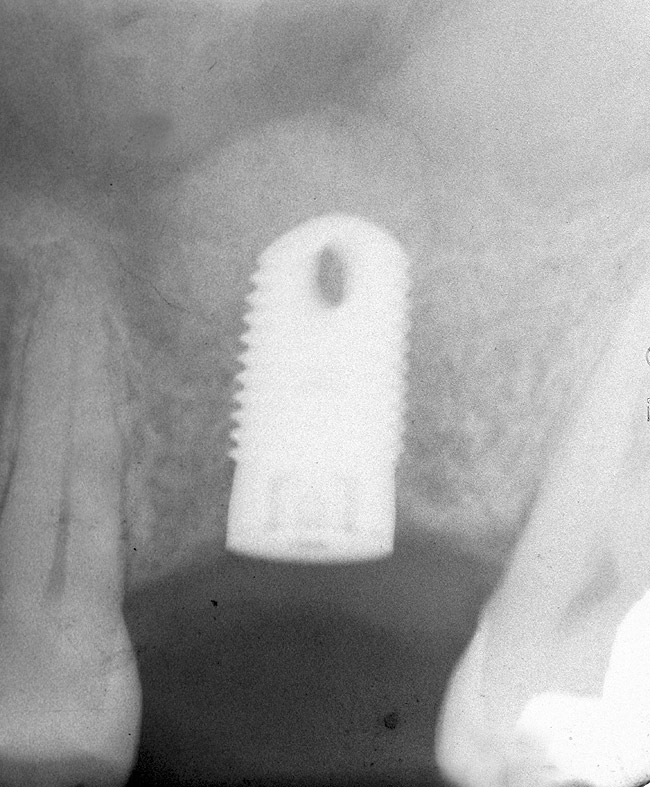

The 2-mm twist drill is used to create an osteotomy 1 mm short of the subantral floor. If any resistance is detected prior to reaching the 3-mm depth, drill penetration must be stopped, because the subantral cortical bone has possibly been reached. Any uncontrolled "push" would penetrate the bone and likely perforate the sinus membrane. A guide pin is then inserted and a radiograph taken to determine if drill penetration has terminated within 1 mm of the subantral floor (Figure 2). If the radiograph indicates that more than 1 mm of bone is present subantrally, the twist drill is used again to penetrate within 1 mm of the sinus floor. Alternately, an osteotomy tip for a piezosurgery unit can be used for this purpose. The final depth of penetration should be verified with another periapical film.

Figure 2  After drilling to a depth of 3 mm with a 2.1-mm twist drill, the guide pin was placed and a radiograph was taken to ascertain if the drill stopped within 1 mm of the subantral floor.

Figure 2

Figure 4  After infracturing the subantral wall with a 3.5-mm osteotome, bone was added and the presence of a dome was confirmed with a radiograph.

Figure 4